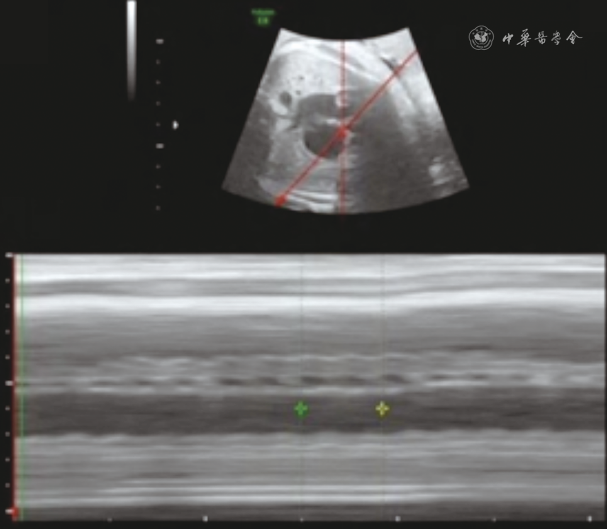

患儿母亲孕期在本院定期产前检查,系统超声及胎儿超声心动图检查均未提示异常,孕38周+6M型超声检查发现胎儿室上性心动过速,胎心率283次/min,剖宫产终止妊娠。

追溯患儿产前超声心动图未能检出三尖瓣下移畸形(图4),但胎龄38周+6时M型超声检查示胎儿心率快,283次/min,律齐,呈1∶1房室传导,VA间期短,诊断为室上性心动过速(图5)。

三尖瓣下移畸形可能导致各种快速性心律失常的发生[12]。右心房增大可能引发心房颤动,房化右心室室壁变薄可能引起室性早搏和室性心动过速,而心室预激致阵发性室上性心动过速的发生风险增加,这也是三尖瓣下移畸形最常见的快速性心律失常。合并有预激的患儿多在胎儿期出现相应表现。本例患儿生后5 d出现阵发性室上性心动过速。而追溯产前超声检查,发现胎龄38周+6时M型超声检查示胎儿室上性心动过速,心率达283次/min,说明M型超声能够较为明确的诊断,但当时未再对心脏结构进行扫查,因而未在胎儿期发现三尖瓣下移畸形。